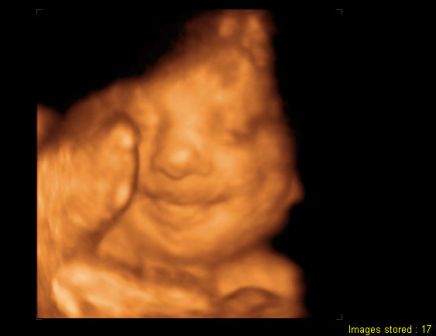

A másik, ma voltunk a 30 hetes UH-on és 4D-n.

Baba jól van, feje lent, lepényem elvándorolt, így már nem állja el a baba útját. Viszont meszesedik a lepényem, aminek még nagyon nem kéne, azt mondták, ez lehet a cukor miatt...

Kissrác nem mutatta meg magát, az egyik oldalát az arcának befúrta a lepénybe, a másikat eltakarta a kezeivel.

Végig le volt árnyékolva, alig készült kép, az is féloldalas.

Fél órát bökdöste a szonográfus, de nem mozdult, hanem kinyújtotta a nyelvét, aztán kiröhögött minket, na szép! :)

És a képek:

Kép Kinyújtja a nyelvét... Kép Aztán kiröhög... Kép És kb ilyen képek lettek :(